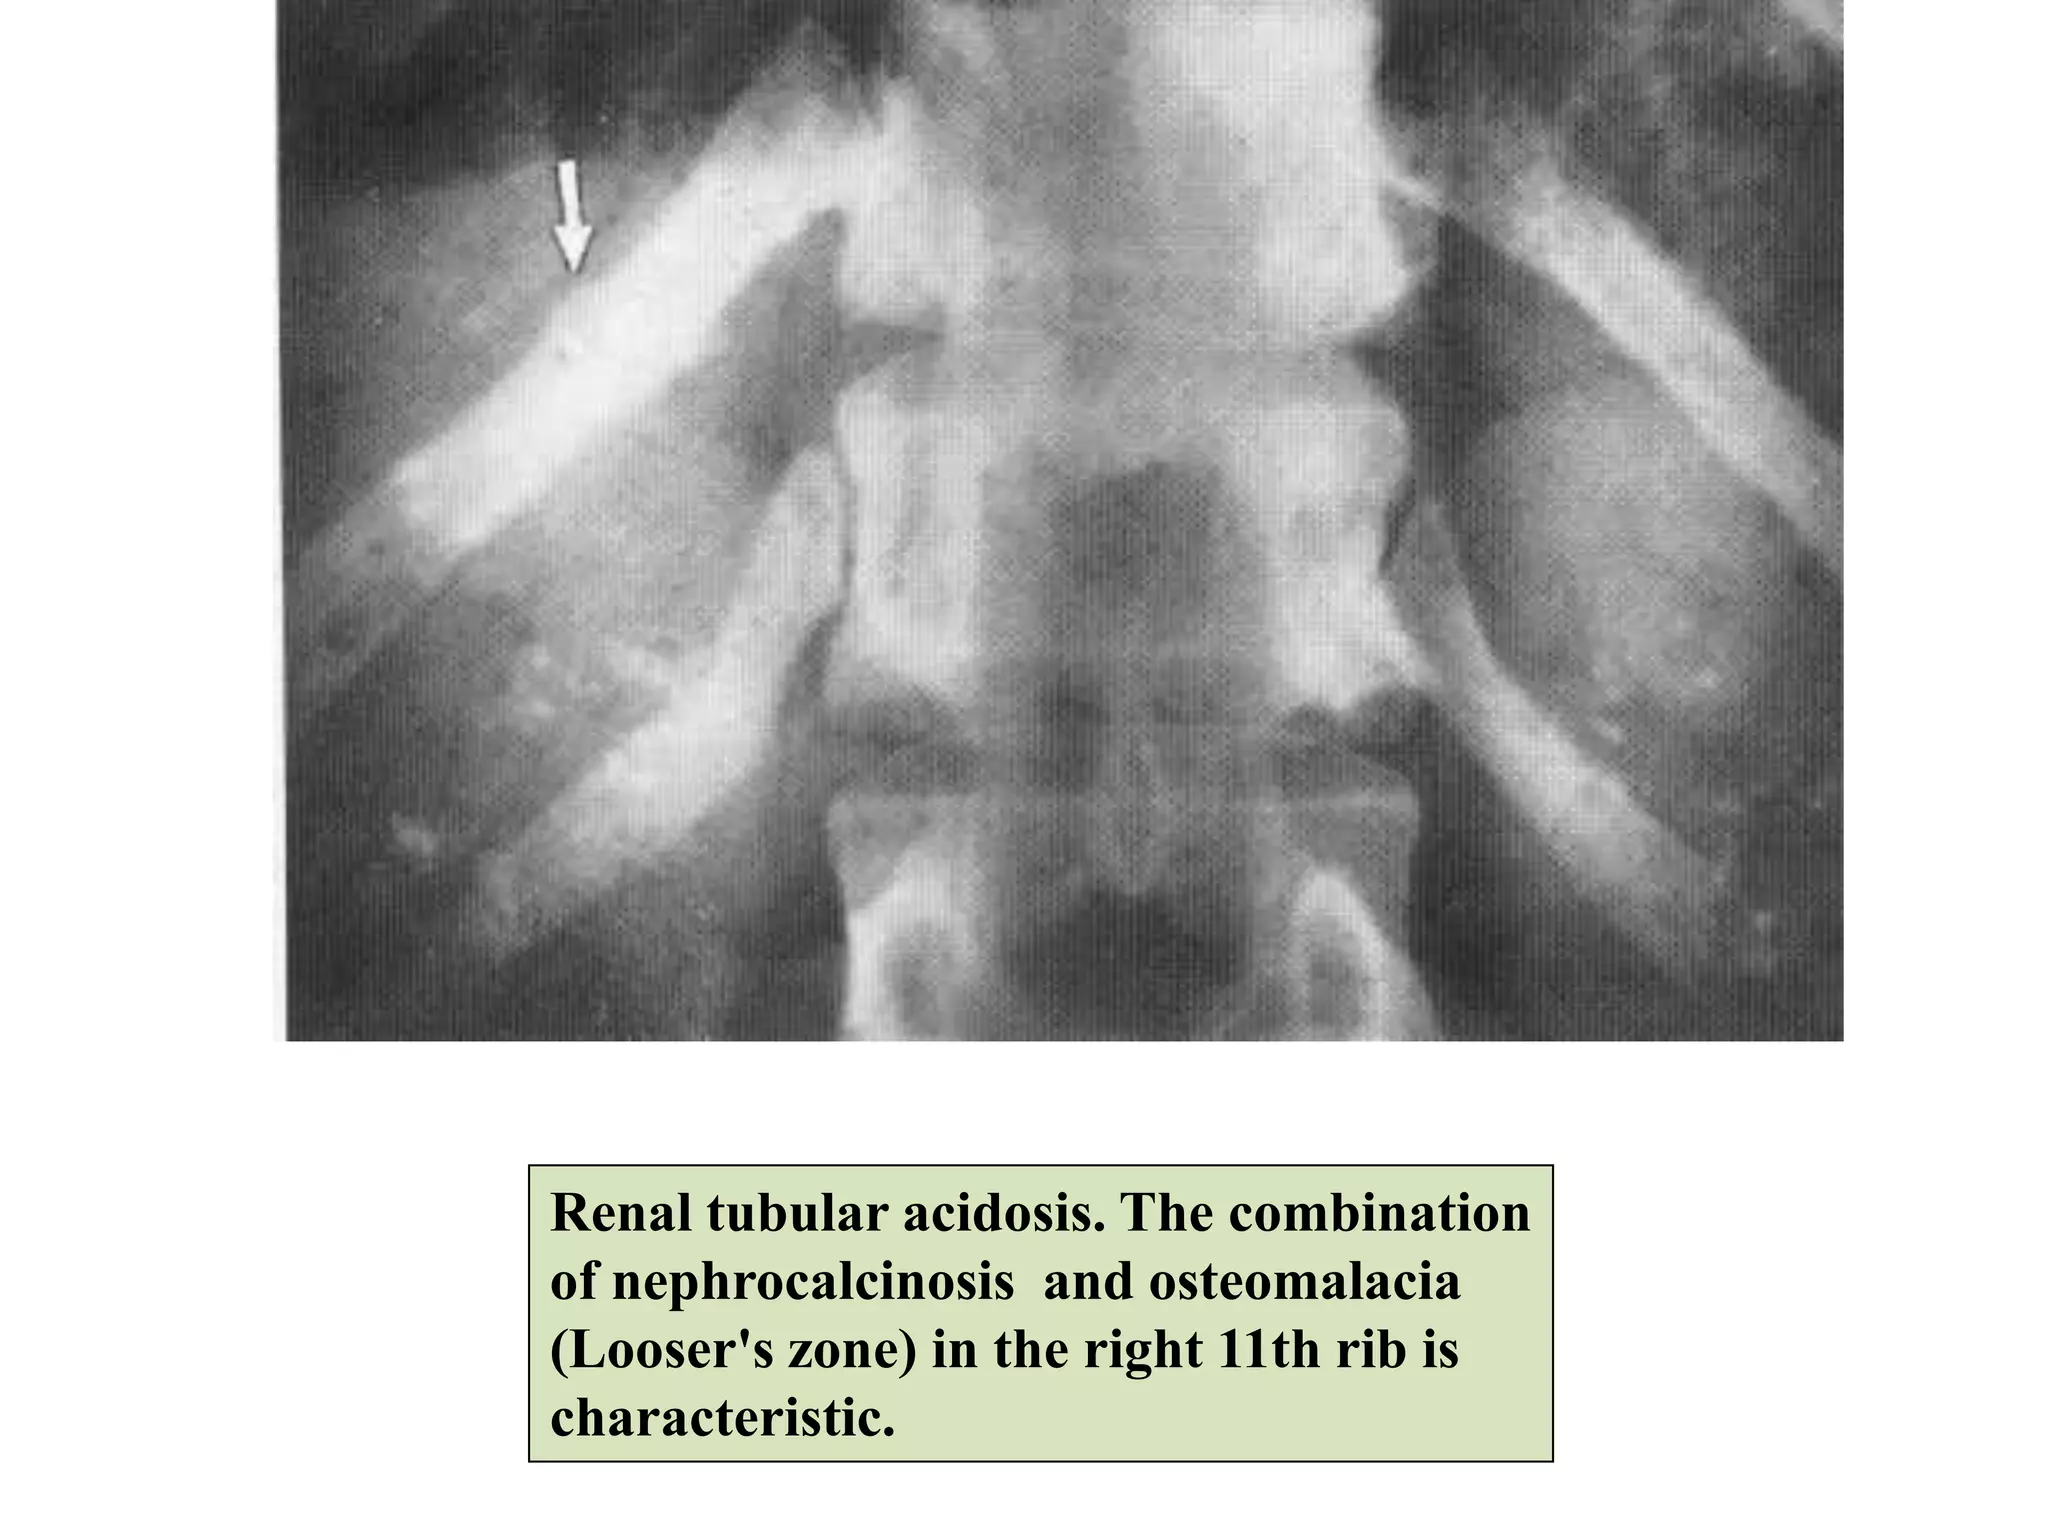

• In renal tubular acidosis, affected patients demonstrate

osteomalacia, nephrolithiasis, nephrocalcinosis.

Renal tubular acidosis. The combination

of nephrocalcinosis and osteomalacia

(Looser's zone) in the right 11th rib is

characteristic.